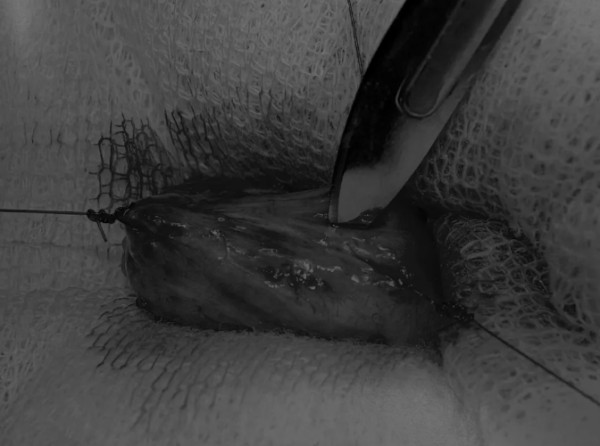

膀胱创面采用单丝合成可吸收缝线缝合,采用外科医生习惯的缝合方式,但注意不要刺穿黏膜层(图6、图7)。

图6 使用简单的连续缝合。尽量不要用针刺穿黏膜层(箭头),以免缝线与尿液接触

图7 缝线应带入足够的切口两侧的膀胱组织,以确保在膀胱充盈时,没有伤口裂开